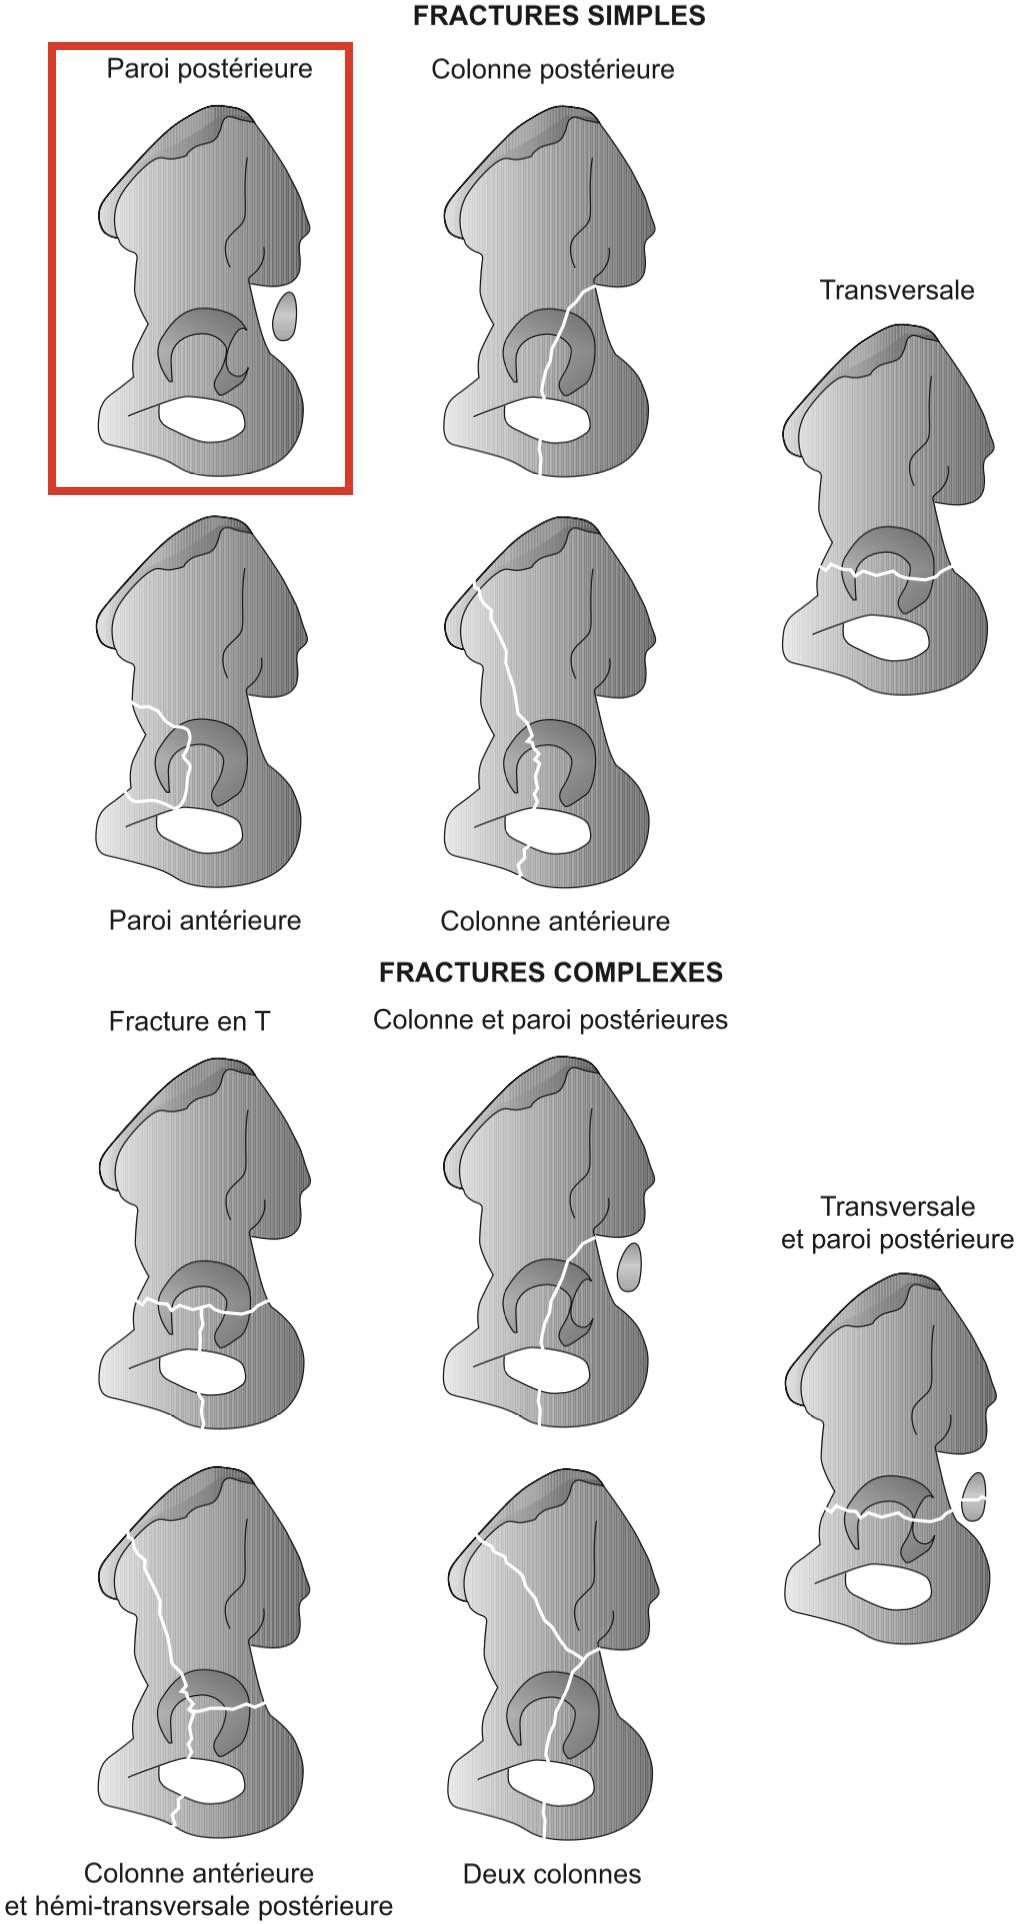

Avulsions apophysaires

Avulsions apophysaires